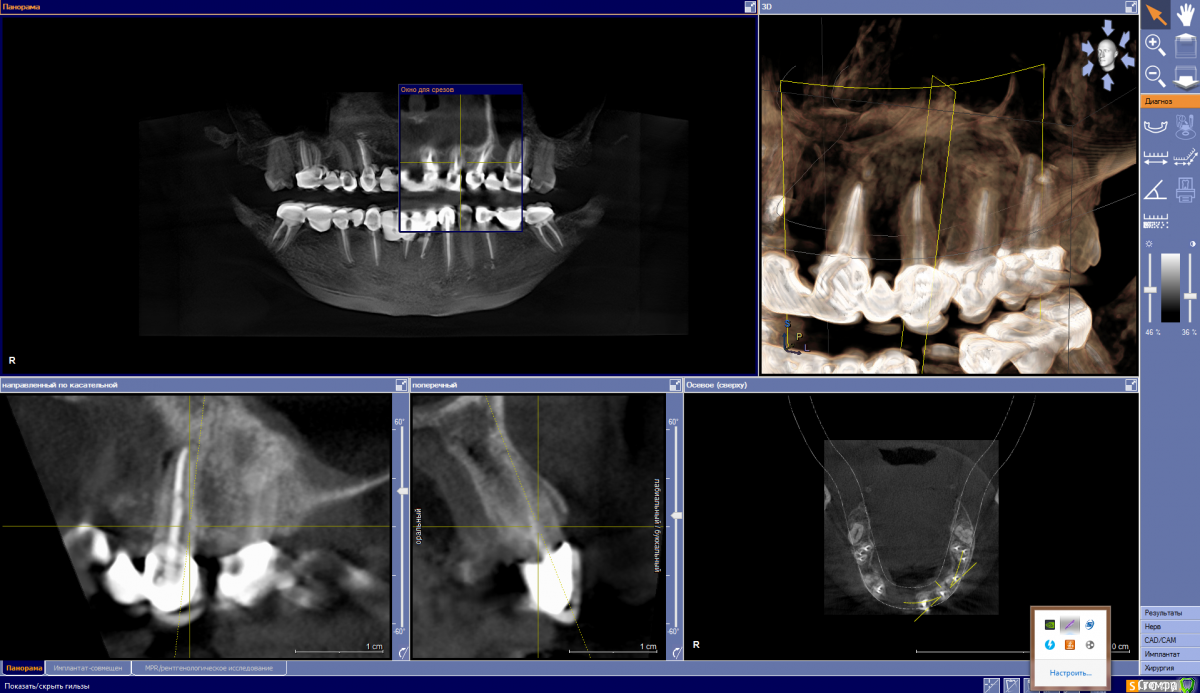

It'sGeorgy Опубликовано 12 мая, 2020 Поделиться Опубликовано 12 мая, 2020 (изменено) ну если прямо сильно нажимаю на него то ощющение небольшой боли вроде есть, а так кушать не больно им, а что скажите по кт, я в срезах не понимаюНа КТ, действительно, есть очаг разрежения костной ткани вокруг этого зуба. При этом, сказать, что каналы запломбированы плохо - тоже нельзя. Я не терапевт, но со своей точки зрения вижу ситуацию так, что у зуба, на самой вершине, есть достаточно выраженный изгиб, что создало огромную трудность для доктора, который зуб лечил. Этот изгиб, к сожалению, запломбировать ко конца не получилось, что привело к развитию хронического воспаления.Повторюсь, я подобным лечением не занимаюсь и мое мнение может быть ошибочным. Поэтому, предлагаю подождать, пока вам ответит кто-то из здешних терапевтов. это не может быть от зуба?Такие ситуации могут быть от зуба, но тогда боль острая и постоянная. Плюс, тогда пациент сам может определить, что его беспокоит конкретный зуб. В вашем случае, как я понимаю, такого нет. Да и судя по снимку, остальные верхние зубы слева в порядке. делала кт 3 раза за годЕсли есть возможность, выкладывайте их тоже. Потому, что на снимке, который вы выложили очень много фоновых шумов, которые создают металлические конструкции во рту(мостовидные протезы). Возможно, по снимкам до изготовления постоянных конструкций будет видно и понятно лучше. Изменено 12 мая, 2020 пользователем It'sGeorgy Ссылка на комментарий

It'sGeorgy Опубликовано 13 мая, 2020 Поделиться Опубликовано 13 мая, 2020 (изменено) Скажите а штифт не помешает для ретроградного пломбирования, или его надо как то убирать? Штифт ставится не на всю длину канала, поэтому вряд ли он помешает. Выделил его красным на прикрепленном снимке. я нашла кт за март 2019 года, сейчас дам вам ссылку, это до протезирования. Сохраните этот снимок куда-нибудь отдельно, чтобы не потерять его. Он четче и информативнее. Изменено 13 мая, 2020 пользователем It'sGeorgy Ссылка на комментарий

ira. k.. 78 Опубликовано 13 мая, 2020 Автор Поделиться Опубликовано 13 мая, 2020 Штифт ставится не на всю длину канала, поэтому вряд ли он помешает. Выделил его красным на прикрепленном снимке. Спасибо доктор. Это у меня киста или что это? Сохраните этот снимок куда-нибудь отдельно, чтобы не потерять его. Он четче и информативнее. Ссылка на комментарий